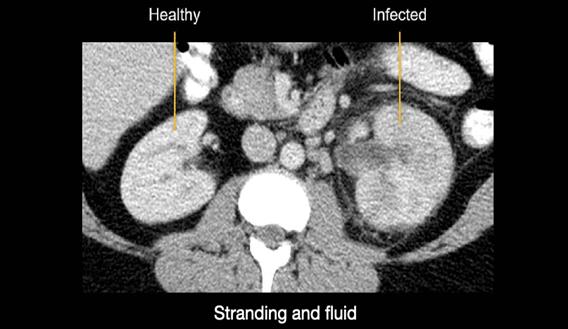

They are often monitored through imaging tests (CT scans and ultrasounds). Small tumours grow slowly and may never be advanced. This is known as active surveillance (American Cancer Society, 2025a).

Figure 1: CT scan of the kidneys

(Creative Commons, 2025)